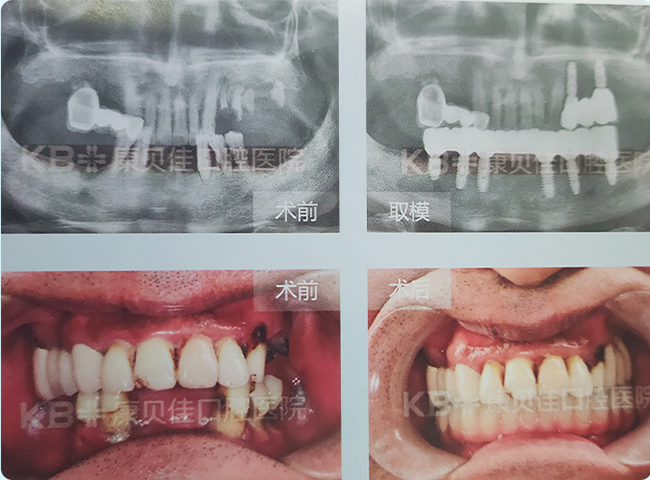

方女士 64岁

全口牙仅剩几颗残根残冠,饮食受限,严重影响生活品质。到院检查后发现其口腔条件差,牙槽骨高度、宽度不足。最终,下颌采用4颗种植体修复,上颌植入8颗植体恢复半口牙,效果非常满意。

治疗方案:

种植8颗恢复半口 种植4颗修复半口